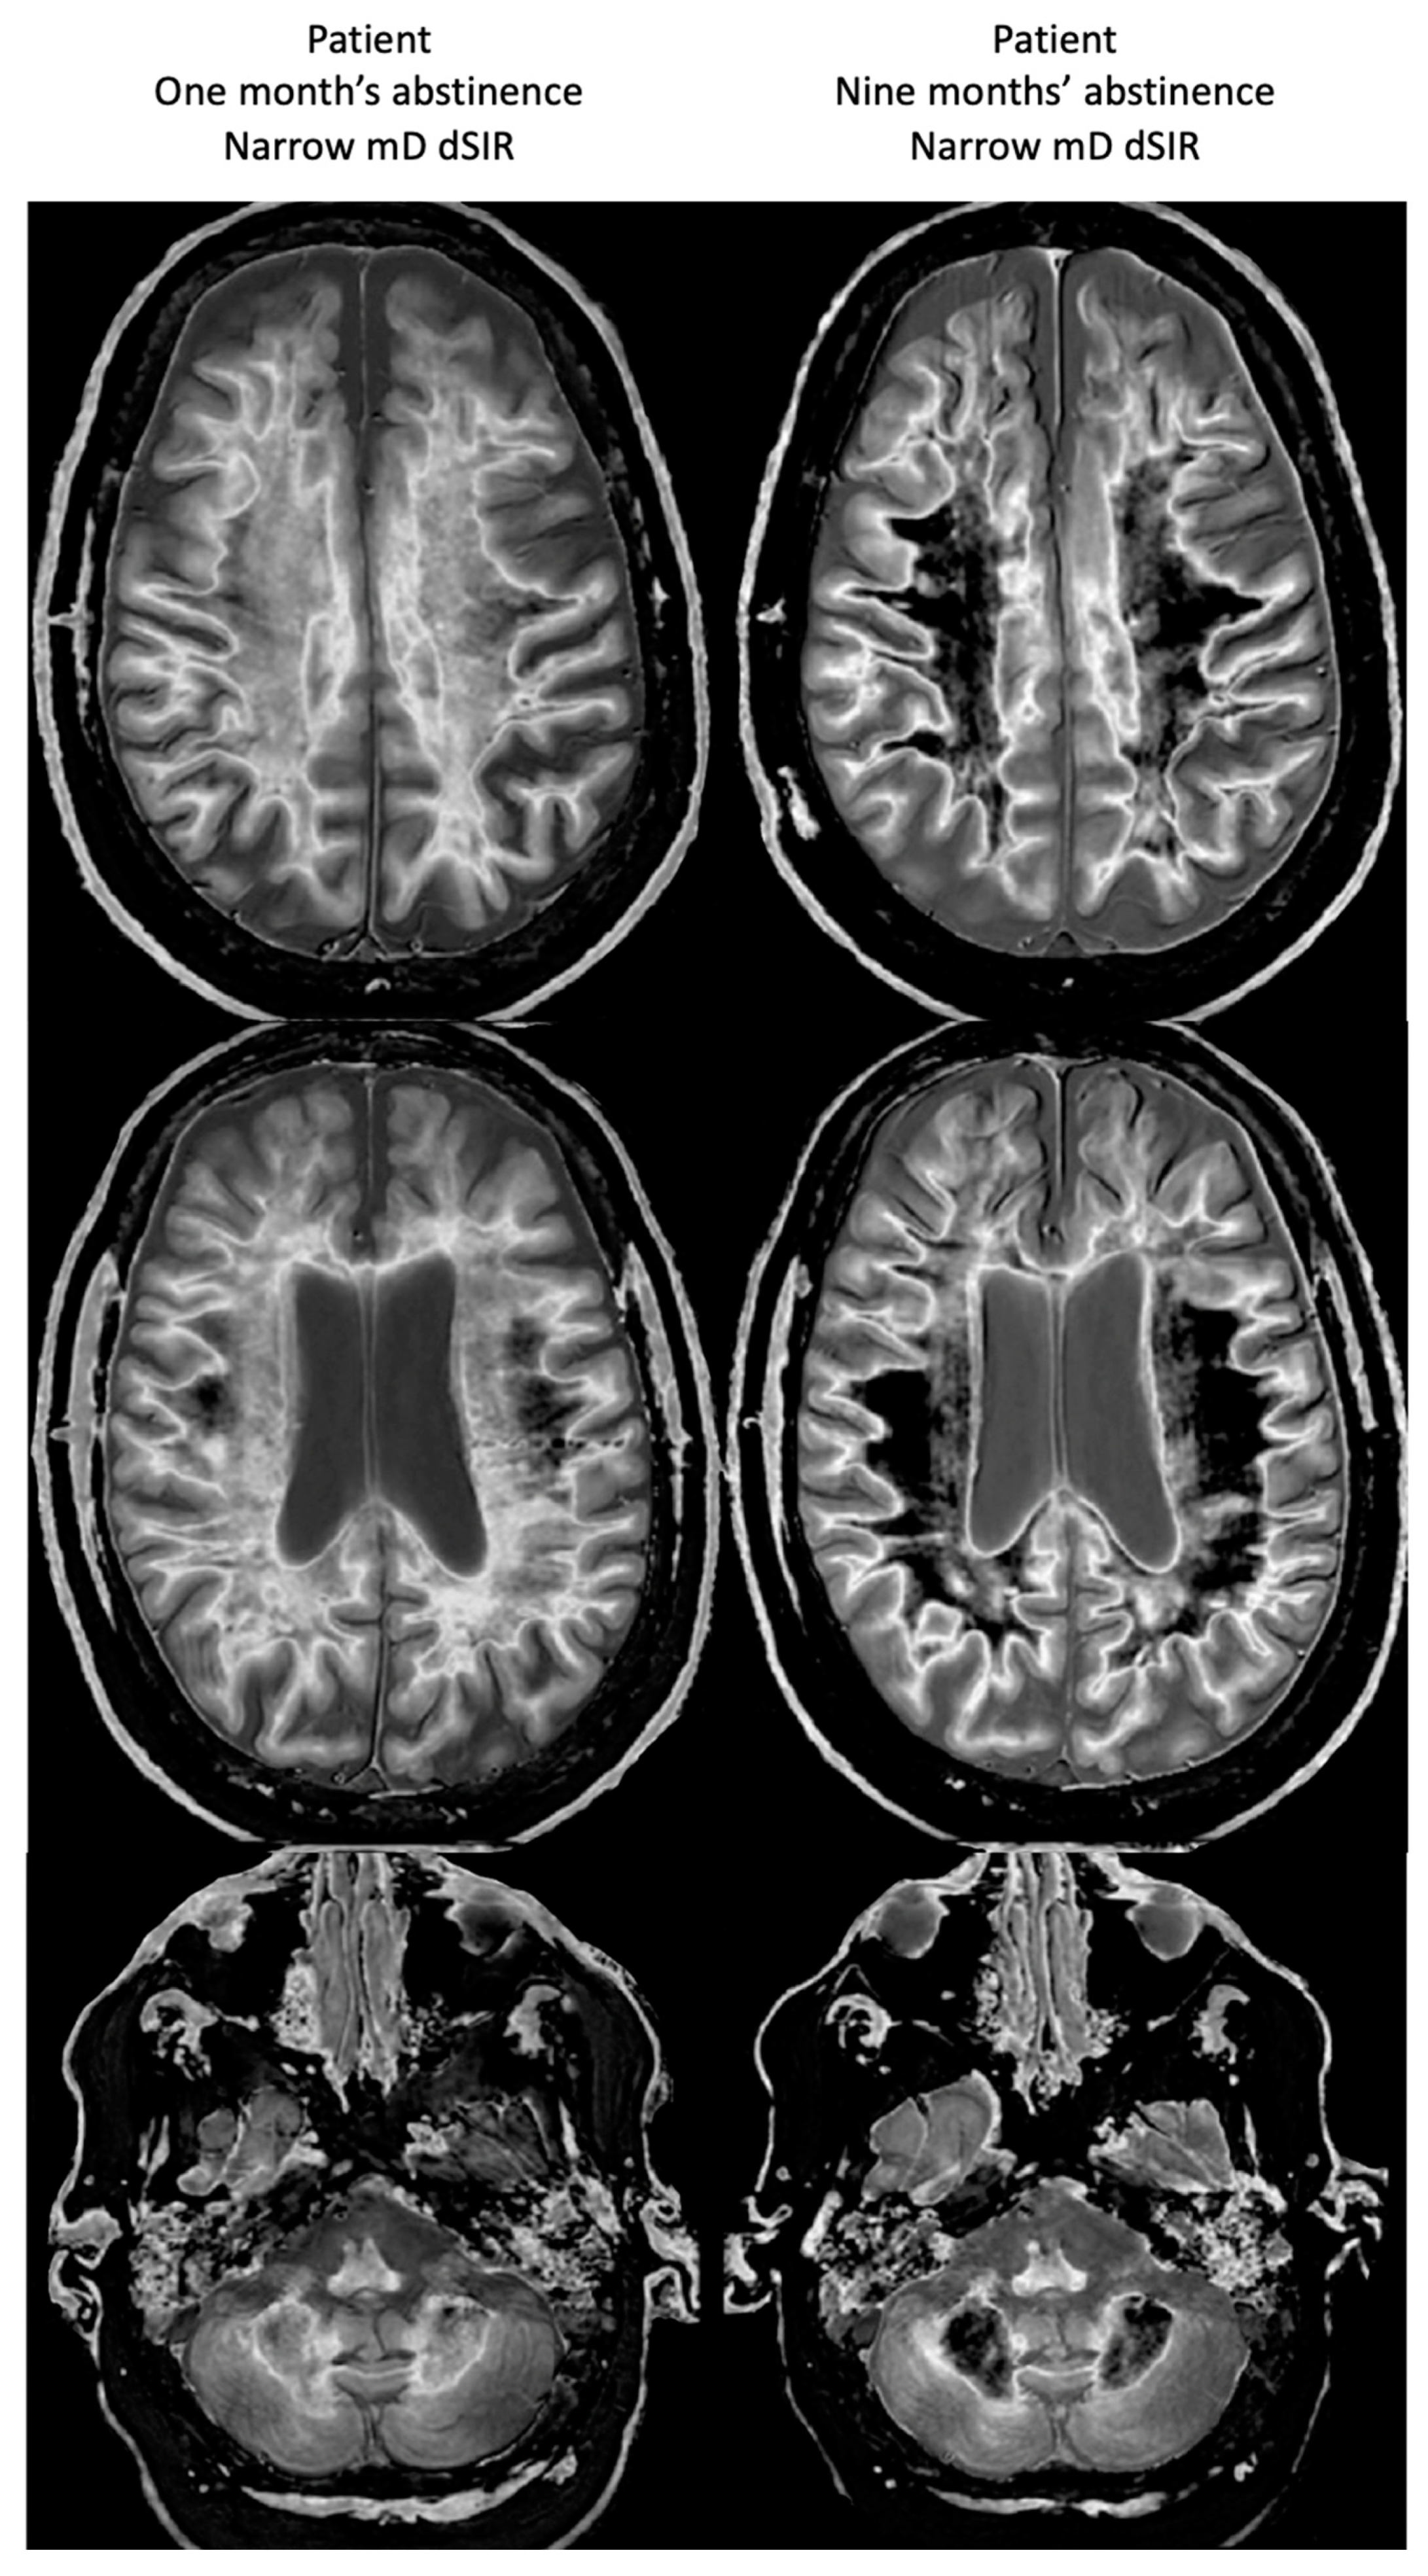

However, there is evidence from postmortem studies that normal appearing tissues seen with MRI using present day protocols may actually be abnormal, and efforts have been made with techniques such as magnetization transfer and magnetic resonance spectroscopy (MRS) to demonstrate these abnormalities. These methods have not been successful enough for them to be included in most contemporary clinical imaging protocols.

At the present time, a third revolution in soft tissue contrast imaging is taking place in which normal appearing tissues seen with state-of-the-art MRI sequences show abnormalities with very high contrast when imaged with newer sequences such as divided subtracted inversion recovery (dSIR). In modelling studies, the dSIR sequence can show ten times more contrast than conventional IR sequences when imaging small changes in T1 due to disease. The small changes in T1 may be insufficient to generate contrast with conventional sequences but the much greater contrast amplification of the dSIR sequence can show obvious abnormalities.

5.6. Normal Appearing White Matter

This term is applied to white matter which appears normal with conventional MRI sequences, but there may be suspicions that this white matter is actually abnormal. Methods of trying to demonstrate this include magnetization transfer, diffusion and proton spectroscopy, none of which have achieved an established role in routine clinical diagnosis of suspected white matter abnormalities. The dSIR approach differs in that changes in a tissue property used in routine clinical diagnosis, i.e., T1 (as with MP-RAGE sequences) are used to demonstrate abnormalities in normal appearing white matter not a different tissue property.